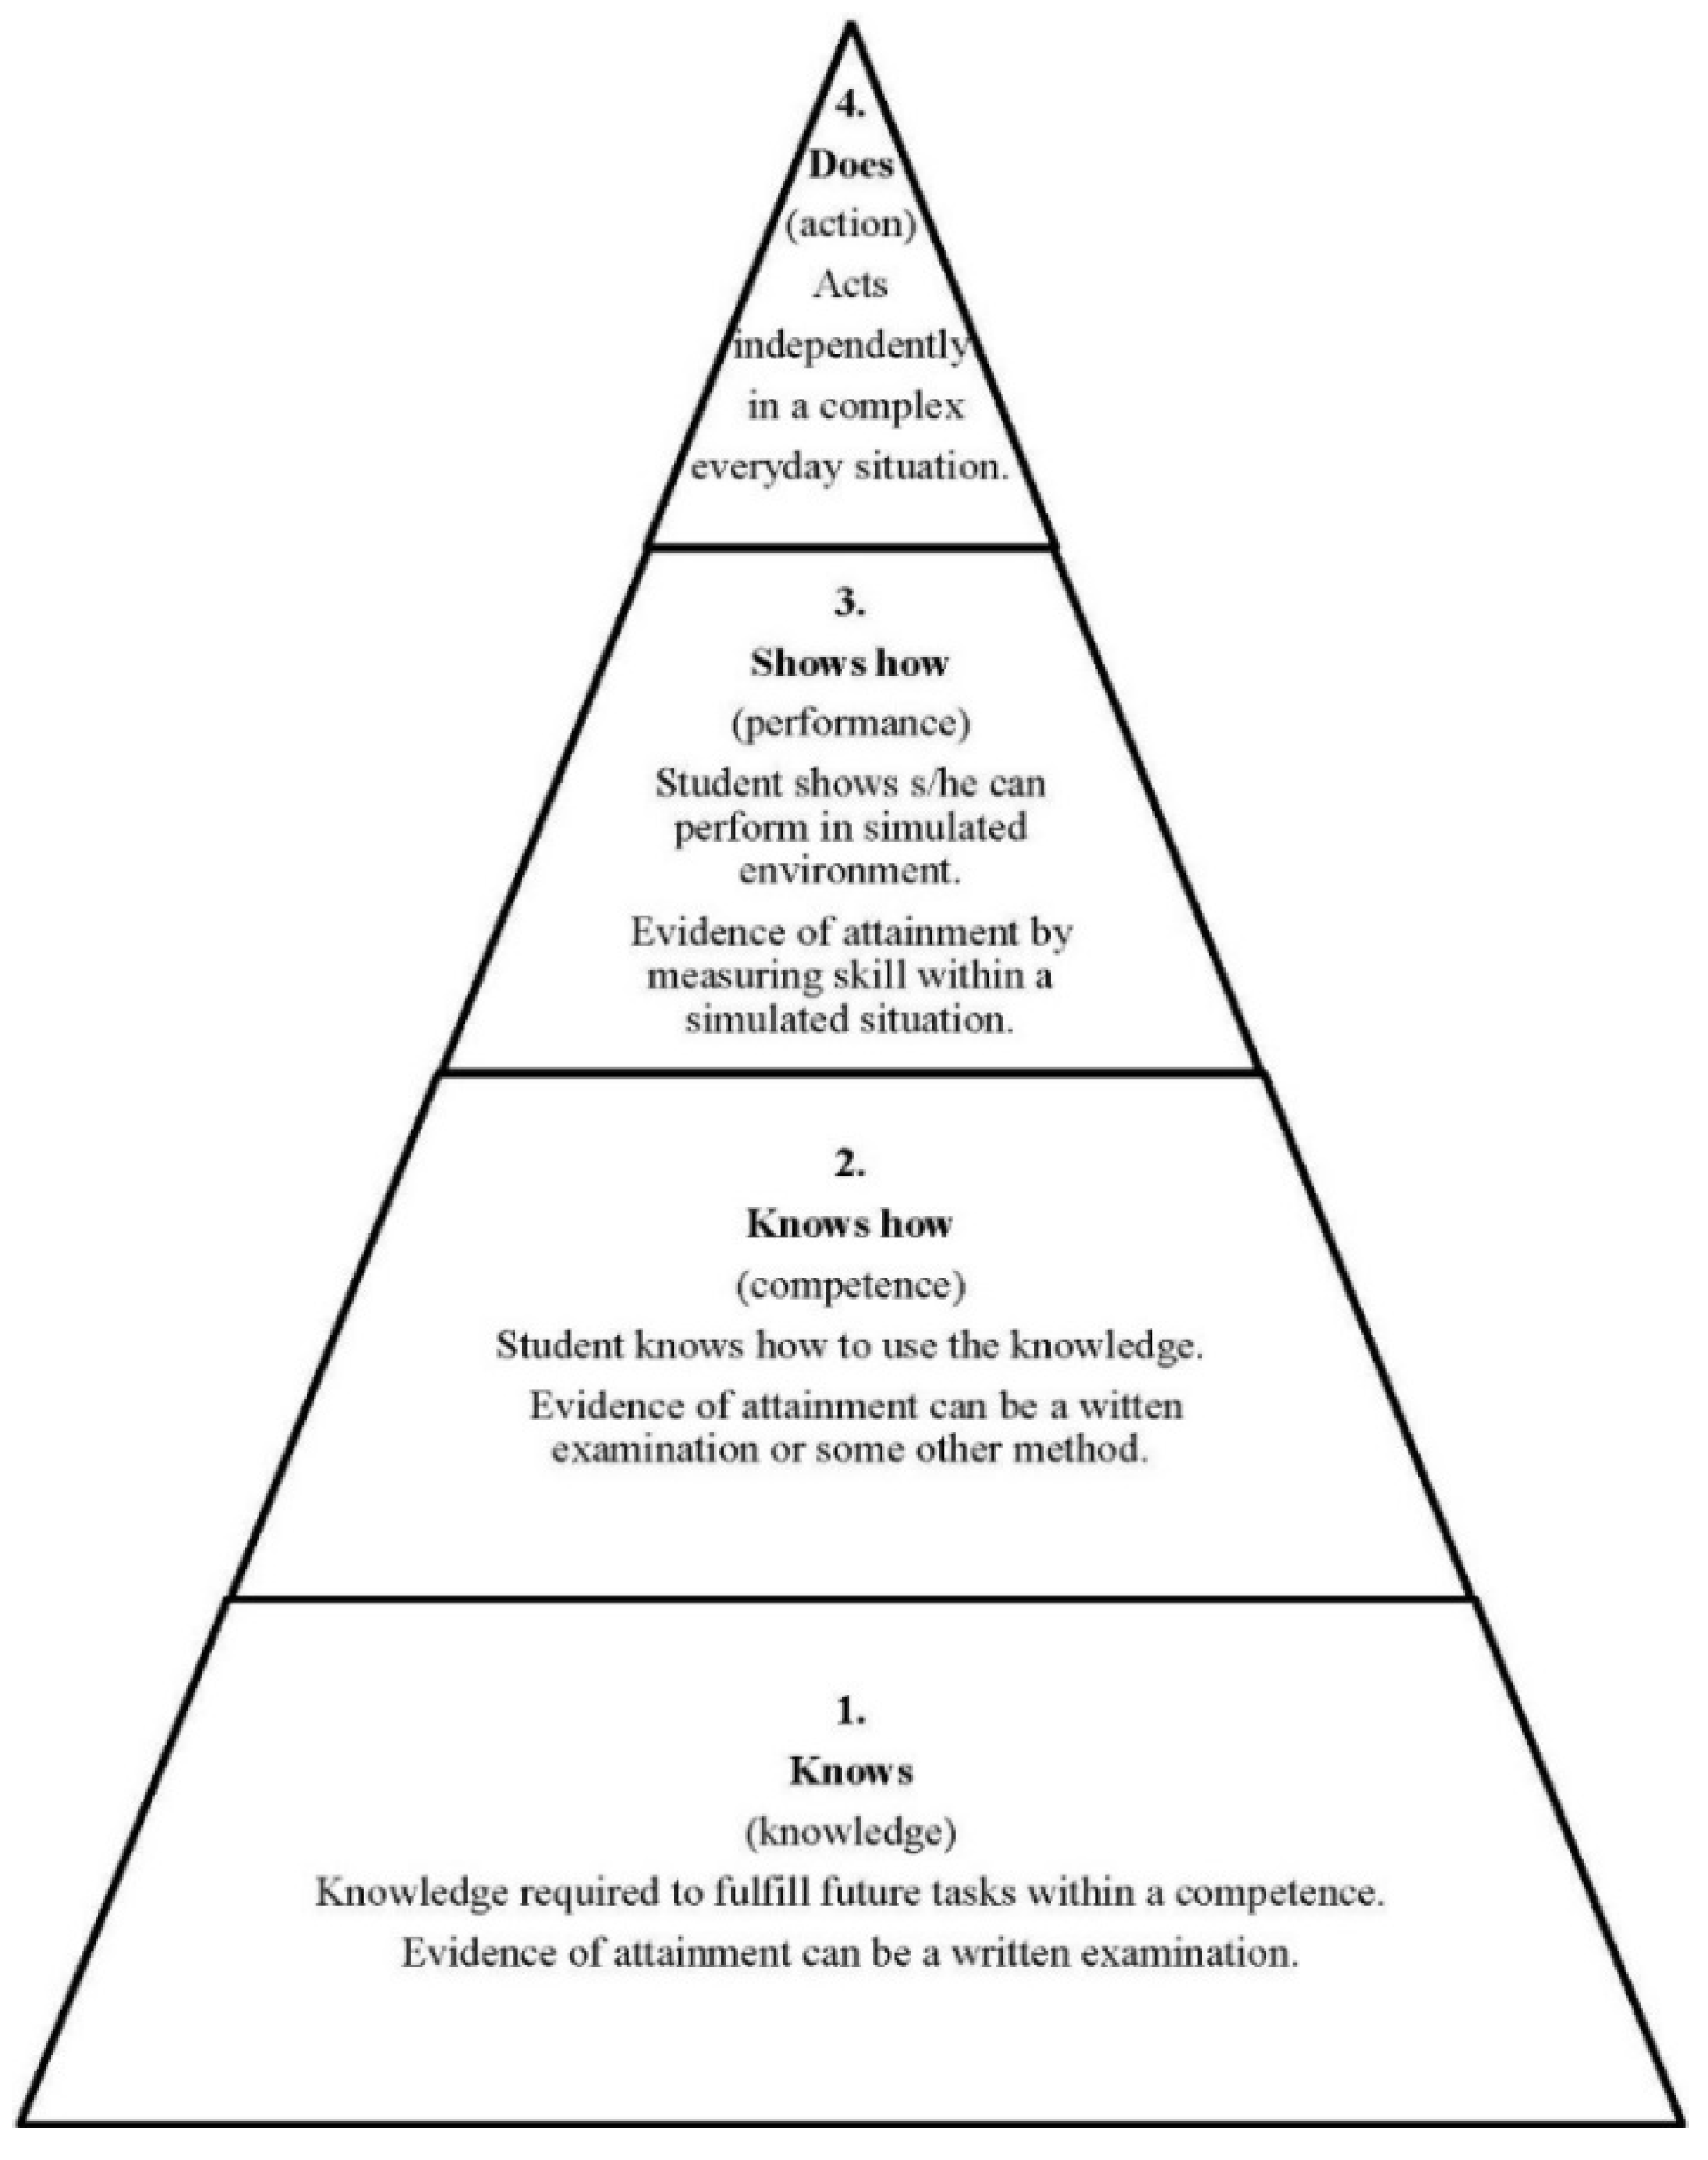

- Fernandez, N.; Dory, V.; Ste-Marie, L.G.; Chaput, M.; Charlin, B.; Boucher, A. Varying conceptions of competence: An Analysis of how Health Sciences Educators Define Competence. Med. Educ. 2012, 46, 357–365. Available online: http://onlinelibrary.wiley.com/doi/10.1111/j.1365–2923.2011.04183.x/abstract (accessed on 12 January 2016). [Google Scholar] [CrossRef] [PubMed]

- Miller, G.E. The assessment of clinical skills/competences/performance. Acad. Med. 1990, 65, 63–67. Available online: http://winbev.pbworks.com/f/Assessment.pdf (accessed on 26 January 2016). [Google Scholar] [CrossRef]

- Carr, S.J. Assessing clinical competency in medical senior house officers: How and Why Should We Do it? Postgrad. Med. J. 2004, 80, 63–66. Available online: http://pmj.bmj.com/content/80/940/63.full.pdf+html. (accessed on 12 January 2016). [Google Scholar] [CrossRef] [PubMed]